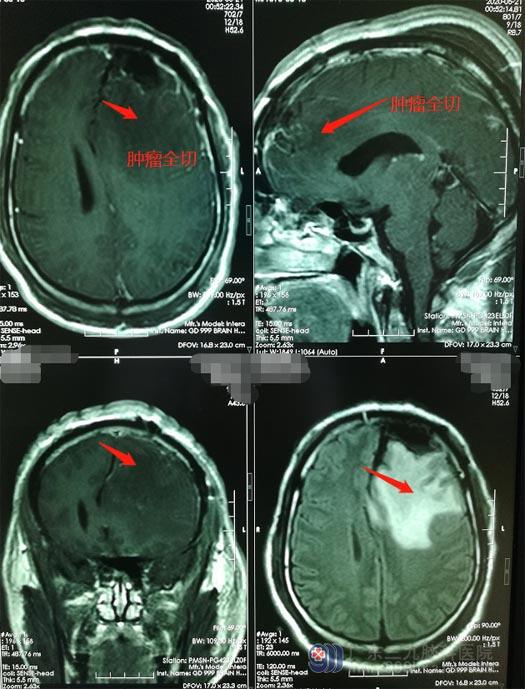

医院副院长、神经外五科主任鲁明查房后指示:陈先生颅内占位考虑肿瘤性病变,病变体积大,并且临近功能区,水肿严重,需尽快手术切除。额叶是脑功能区,稍有不慎,可导致肢体偏瘫,言语功能障碍等。经过慎重的术前讨论后,决定采用术中唤醒麻醉,利用神经电生理技术精确定位脑重要功能区并探询病变与功能区的关系,最大限度切除肿瘤并保留功能区。术中,见肿瘤的血供丰富,术中冰冻病理提示脑膜瘤,显微镜下将肿瘤全切。

手术结束,陈先生返回病房时已神志清醒,言语正常,四肢活动自如;不久就可以放心地出院了。